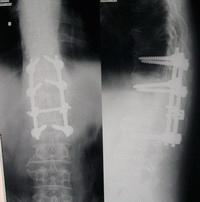

椎弓结核系指病变限于椎弓根、椎板、棘突或横突,而不是继发于椎体结核扩展到椎弓根、横突或上下关节突的病变。本病较为少见,占脊椎结核0.8%~1%,另一组10531例脊椎结核中有45例,占2.3%。发病率少,常出现肿块脓肿或窦道脊柱无畸形活动无明显受限。